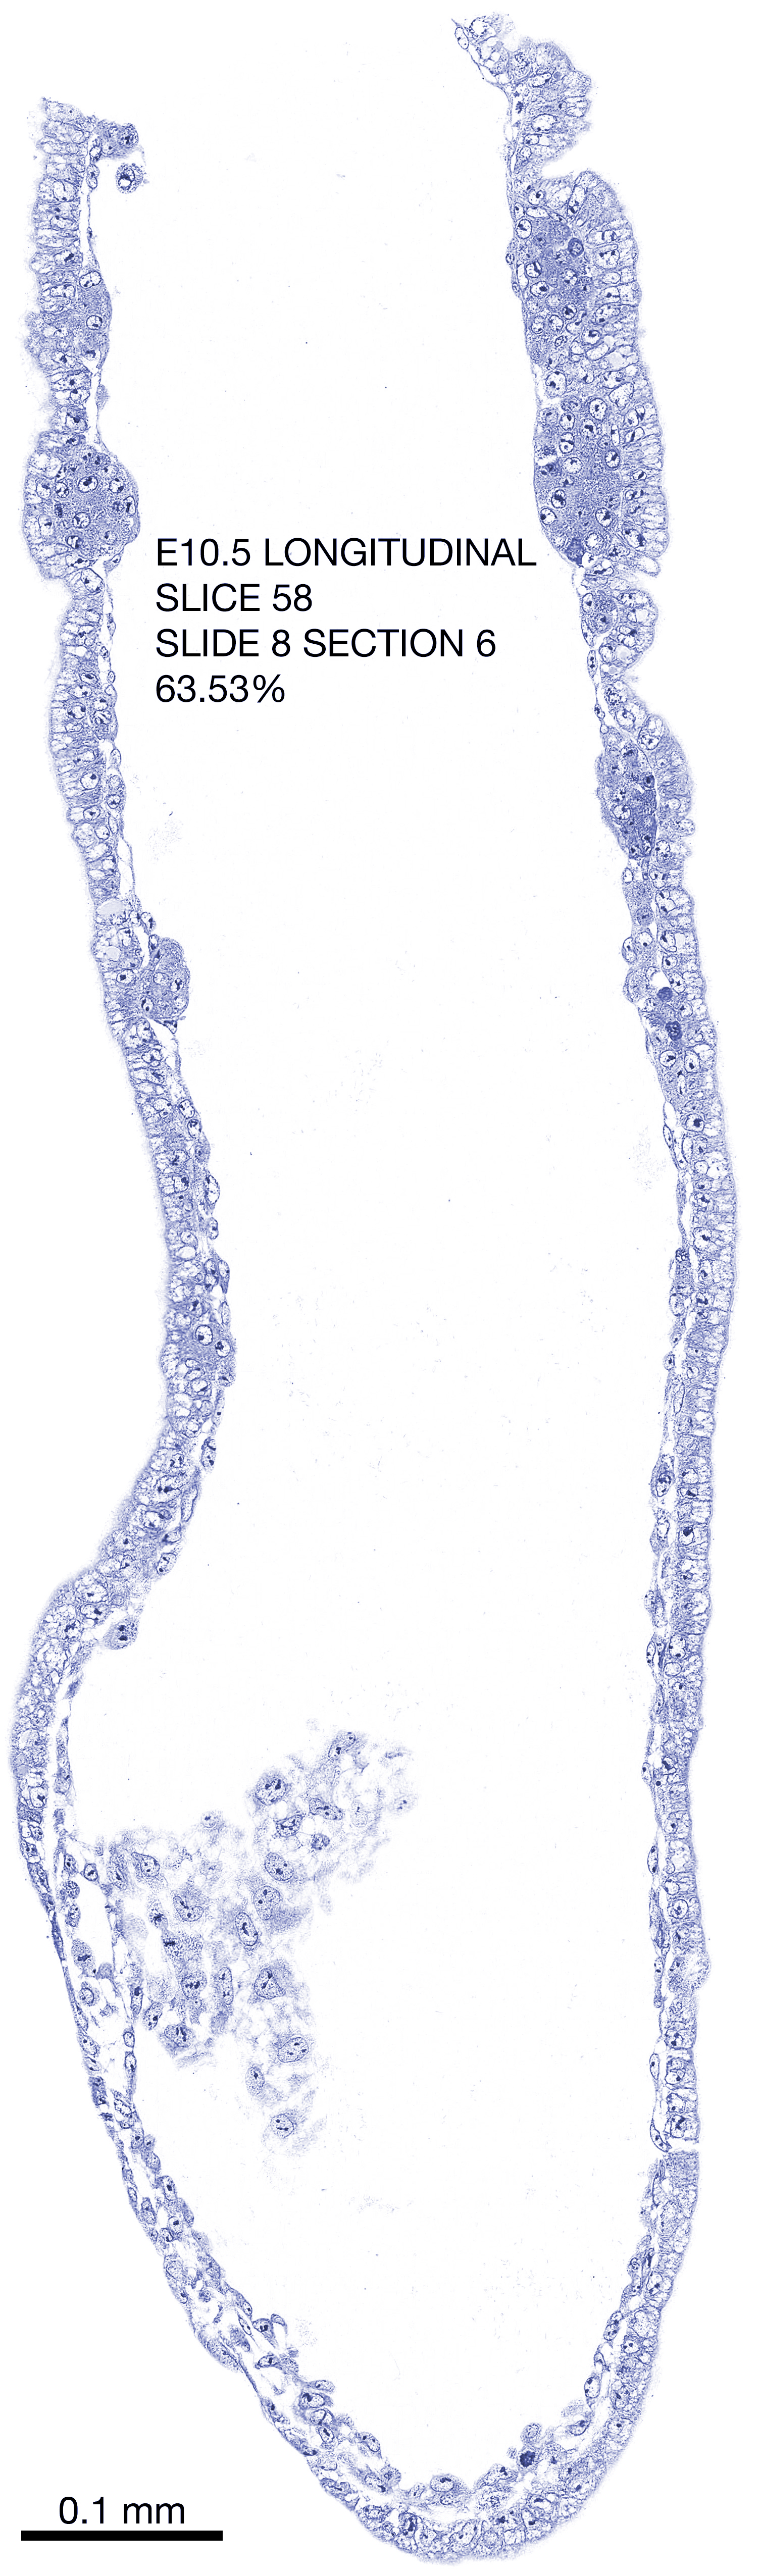

E10.5 Longitudianal Archive This page contains jpg files of ALL SLICES (each 3µm thick) that were scanned of the E10.5 longitudinally cut specimen. Download: Large | High Res Download: Large | High Res Download: Large | High Res Download: Large | High Res Download: Large | High Res Download: Large | High Res Download: Large | High Res Download: Large | High Res Download: Large | High Res Download: Large | High Res Download: Large | High Res Download: Large | High Res Download: Large | High Res Download: Large | High Res Download: Large | High Res Download: Large | High Res Download: Large | High Res Download: Large | High Res Download: Large | High Res Download: Large | High Res Download: Large | High Res Download: Large | High Res Download: Large | High Res Download: Large | High Res Download: Large | High Res Download: Large | High Res Download: Large | High Res Download: Large | High Res Download: Large | High Res Download: Large | High Res Download: Large | High Res Download: Large | High Res Download: Large | High Res Download: Large | High Res Download: Large | High Res Download: Large | High Res Download: Large | High Res Download: Large | High Res Download: Large | High Res Download: Large | High Res Download: Large | High Res Download: Large | High Res Download: Large | High Res Download: Large | High Res Download: Large | High Res Download: Large | High Res Download: Large | High Res Download: Large | High Res Download: Large | High Res Download: Large | High Res Download: Large | High Res Download: Large | High Res Download: Large | High Res Download: Large | High Res Download: Large | High Res Download: Large | High Res Download: Large | High Res Download: Large | High Res